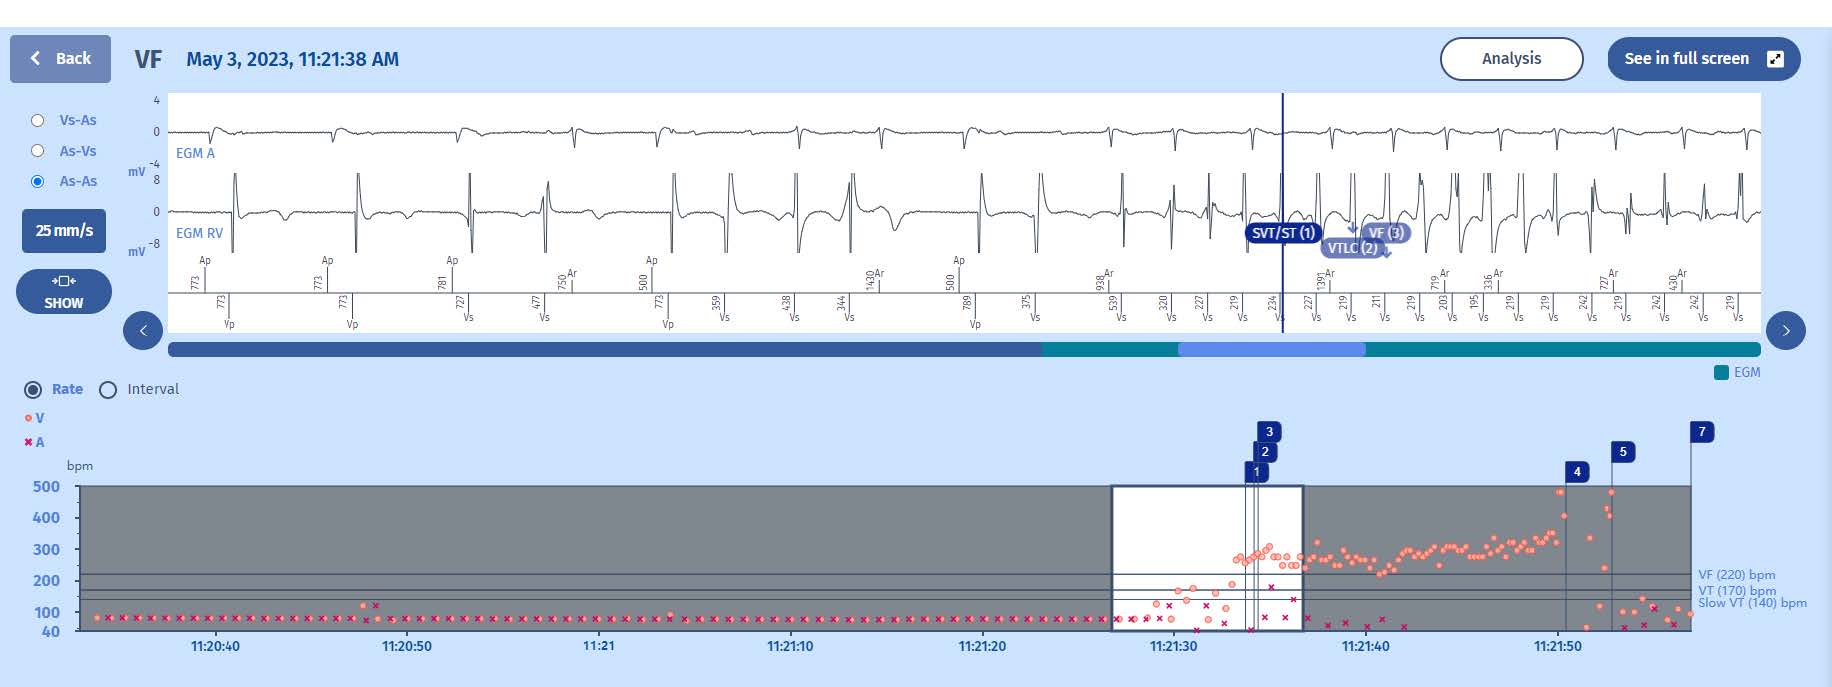

The interval plot shows a stable atrial and ventricular rhythm (probably paced as the intervalsseem fixed) with a sudden acceleration of ventricular events, beginning with extrasystoles and continuing with a more organized tachycardia in the VF zone. After the shock (marker 4), there are again a few extrasystoles before the return to slow rhythm).

The beginning of the tachycardia is very typical with first extrasystoles disturbing the rhythm and then an organized ventricular arrhythmia which speeds up and becomes more organized after a few cycles. This is called “warming-up” and is often seen in the beginning stage of a fast ventricular tachycardia. As MicroPort ICDs use a very fast counter (6 out of 8), we often see an early SVT marker during this period as there are 6 cycles in the VT zone (including 2 extrasystoles) but these cycles are unstable and therefore the discrimination algorithm classifies the events as “supraventricular”(SVT). When we click on the marker, in the window we find the word: Unstable, which confirms the normal algorithm behavior.

As the arrhythmia speeds up into the VF zone, there is fast appearance of the VF marker and theVF persistence starts (at a value of 1) while the VT persistence increases to 2 (it was 1 during the previous cycle at the same time as the VTLC marker). There is no discrimination in the VF zone in MicroPort ICDs so any 6/8 events in the VF zone will result in a VF marker. There is however another check of stability which is required to make the choice between Fast-VT or FV therapies but more about this later. After filling of the VF persistence (20 cycles), the charge begins.

After the charge has completed, there is confirmation of the tachycardia and the shock is delivered. The shock terminates the VT. Interestingly, there is a new VF marker which is caused by some low amplitude noise on the ventricular channel, associated with some late post-shock artifacts. But the persistence is reset soon after when the VF majority is lost (No majority marker). The episode is concluded when the Slow majority is reached.